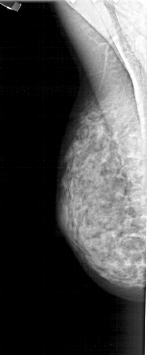

A_1269_1.LEFT_MLO

LEFT_MLO LINES 4966 PIXELS_PER_LINE 2086 BITS_PER_PIXEL 12 RESOLUTION 43.5 NON_OVERLAY